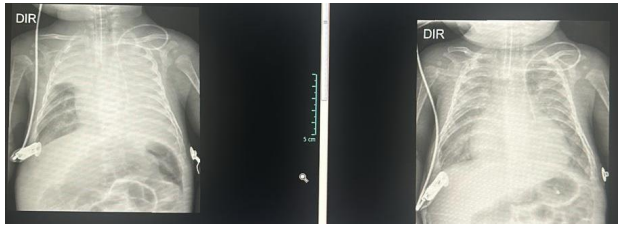

Paciente de 3 meses, pesando 5Kg, nascido termo, parto vaginal e com calendário vacinal atualizado está internado com hipótese diagnóstica de bronquiolite. No segundo dia de internamento, evoluiu com piora do padrão respiratório, com importante tiragem subcostal, tiragem intercostal, retração de fúrcula e batimentos de asa nasal. A ausculta pulmonar, que era simétrica e com estertores e sibilos difusos, evoluiu com assimetria e significativa redução à esquerda. Após 2 horas de ventilação não invasiva, paciente seguia com quadro de desconforto respiratório e saturação periférica de oxigênio máxima de 87% com FiO2 50%. Você optou por intubar paciente.

Seguem as imagens referentes ao momento imediatamente posterior à intubação e 6 horas após o início da ventilação mecânica.

Diante do caso, qual complicação o paciente apresentou, sua conduta e materiais utilizados?